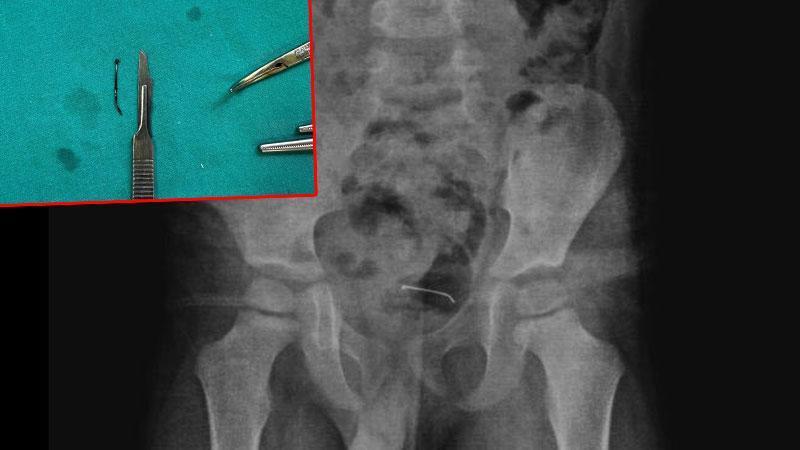

Güroymak'ta sürekli karın ağrısı şikayeti çeken 5 yaşındaki çocuk, ailesi tarafından çeşitli sağlık kuruluşlarına götürüldü. Sonuç alamayan aile, en son Tatvan Devlet Hastanesi'ne başvurdu. Burada çekilen röntgende, çocuğun mesane duvarında metal bir cisim olduğu belirlendi. 9 ay önce yutulan ve vücutta kalan 3 santimetrelik toplu iğnenin mesane duvarına yapıştığı tespit edilince ameliyata karar verildi.

Tatvan Devlet Hastanesi Çocuk Cerrahi Uzmanı Op. Dr. Tahsin Onat Kamçı tarafından gerçekleştirilen operasyonla, toplu iğne başarılı bir şekilde çıkarıldı. Gözlem altında tutulan çocuk, birkaç gün sonra taburcu edildi. Op. Dr. Tahsin Onat Kamçı "Cerrahi operasyonla 3 santimetre civarındaki toplu iğneyi çıkardık. Hastayı birkaç gün takipte tuttuk. Genel sağlık durumu iyi olan hastamızı taburcu ettik. Kesici ve delici cisimler çok tehlikeli. Bu gibi cisimlerin çocukların ulaşabileceği yerlere bırakılmaması gerekiyor" dedi.